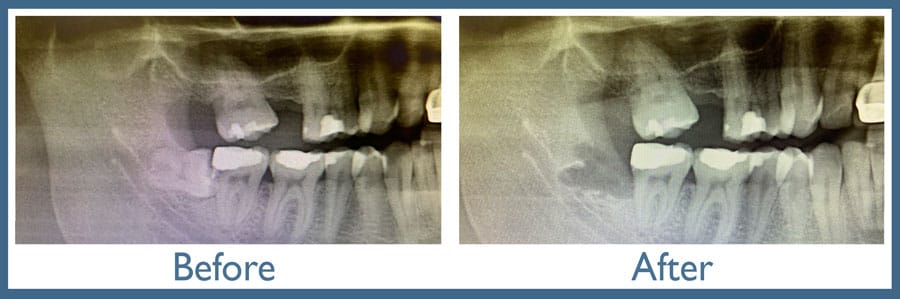

Latest imaging technology: